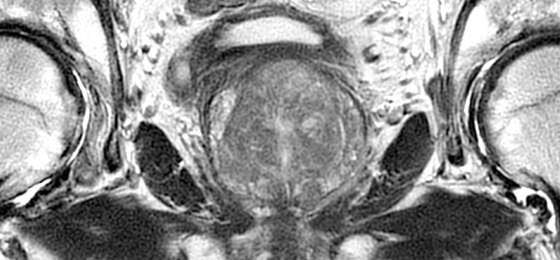

Make no substitutes for image quality

Clearly consistent images

Simply better compared to conventional coil technology.